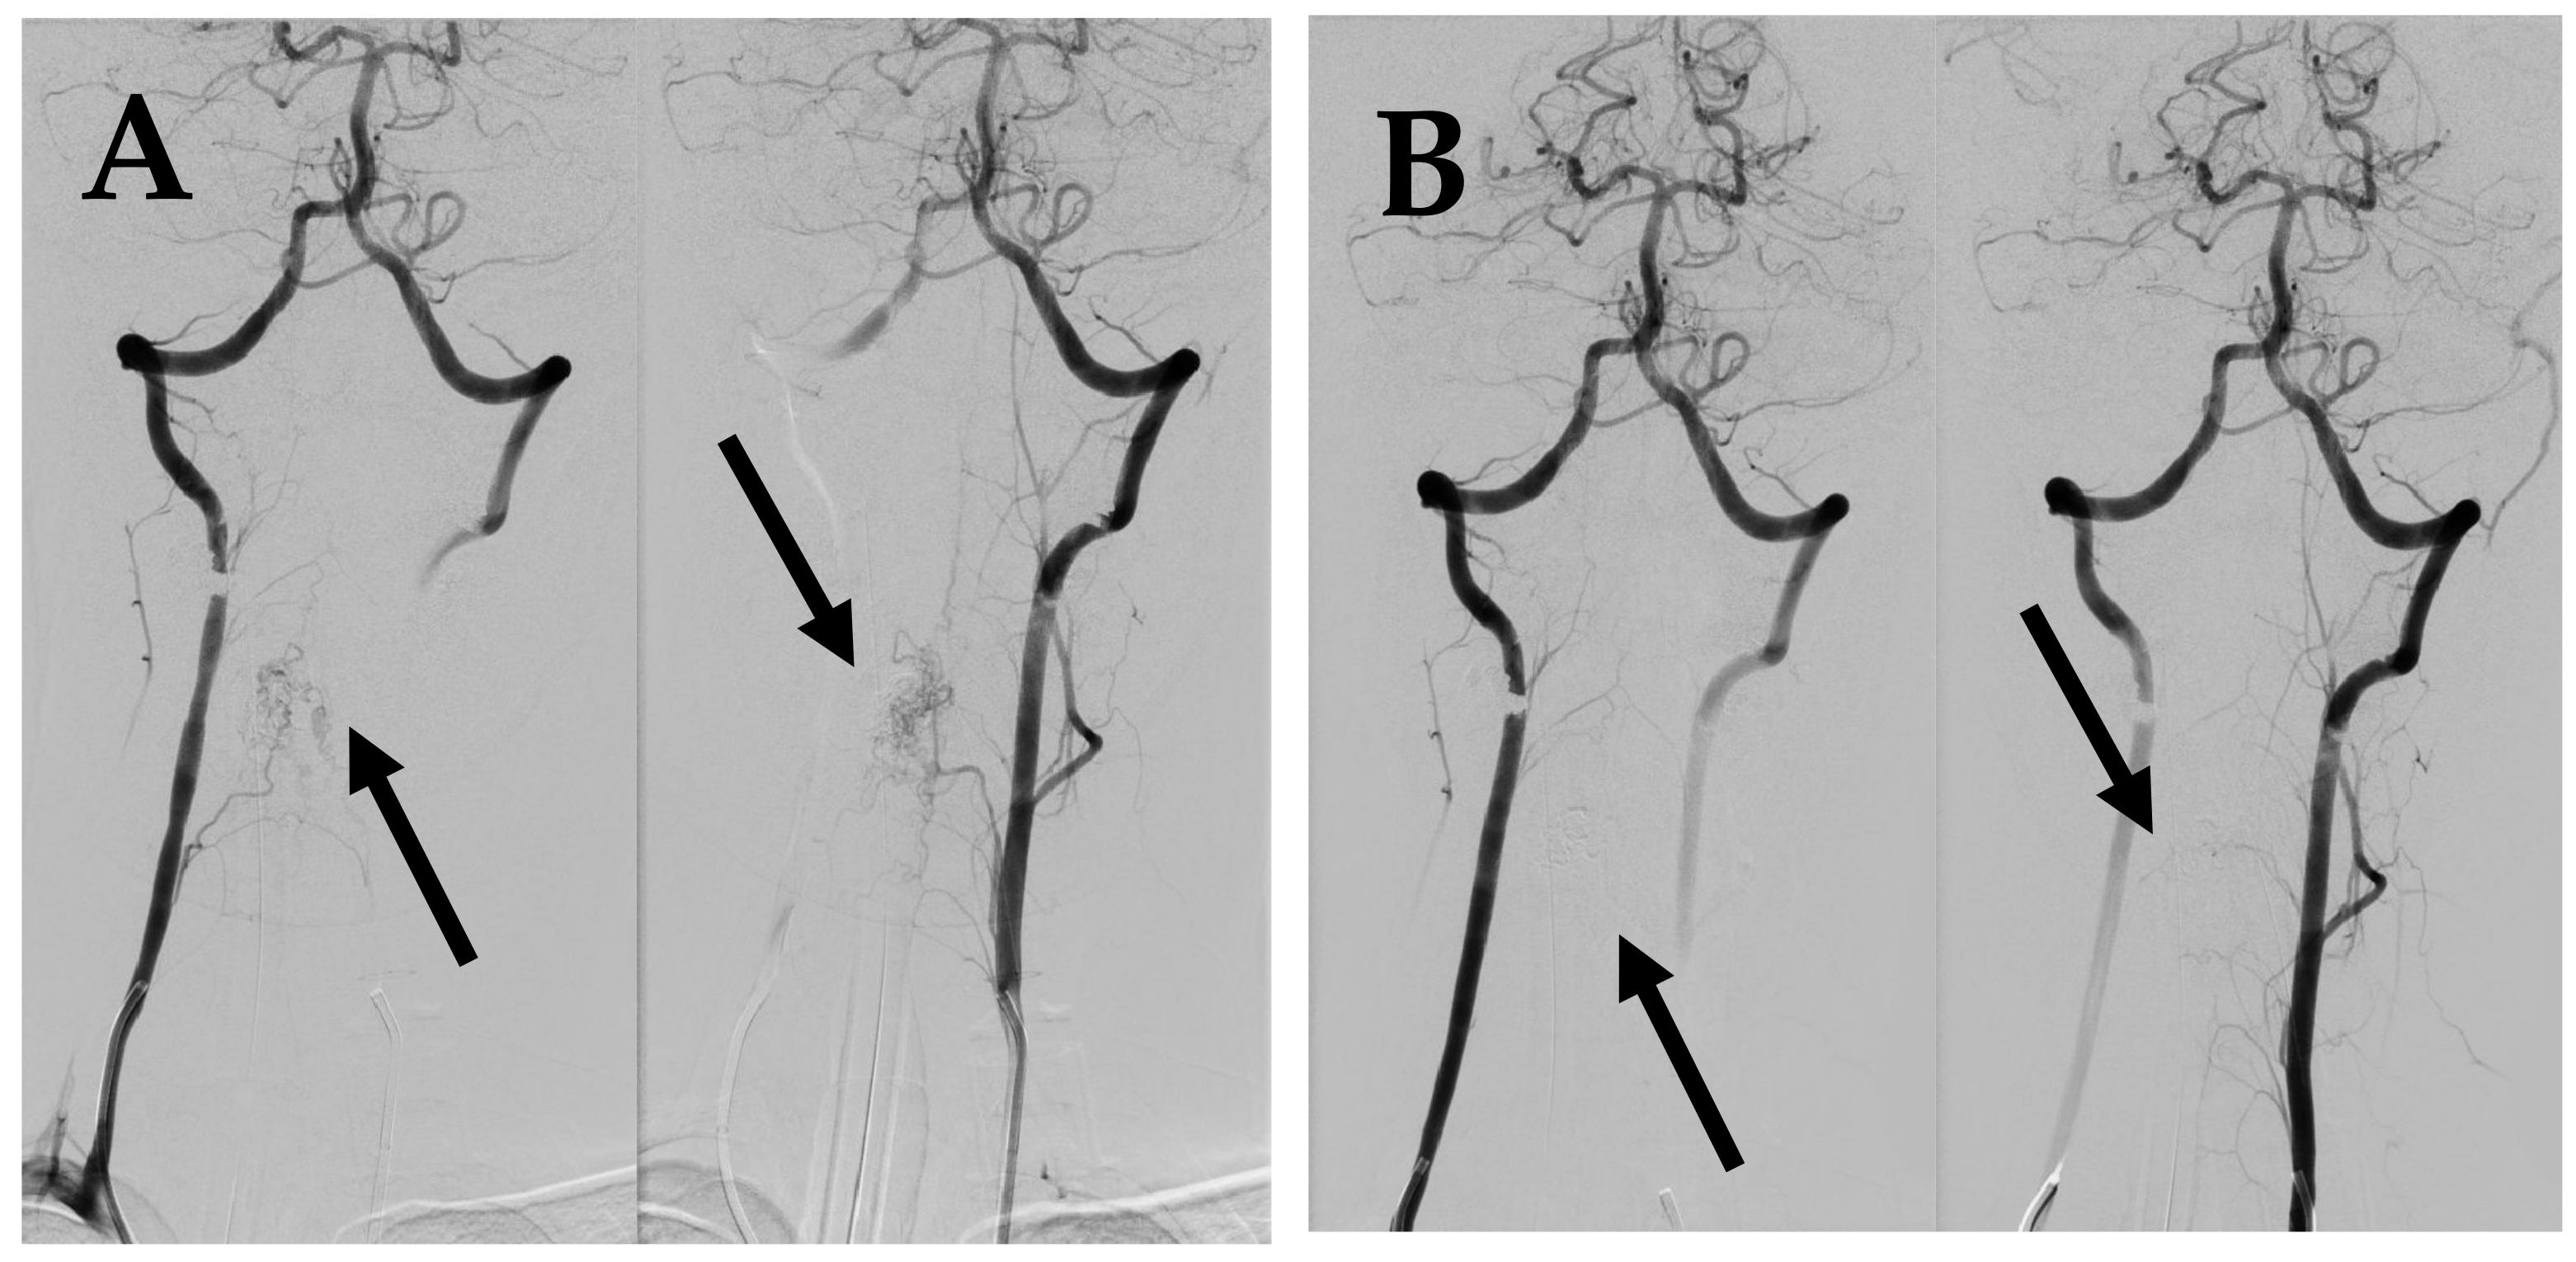

7.1. First Episode (2011)

7.2. Second Episode (2020)

7.3. Third Episode (2023)